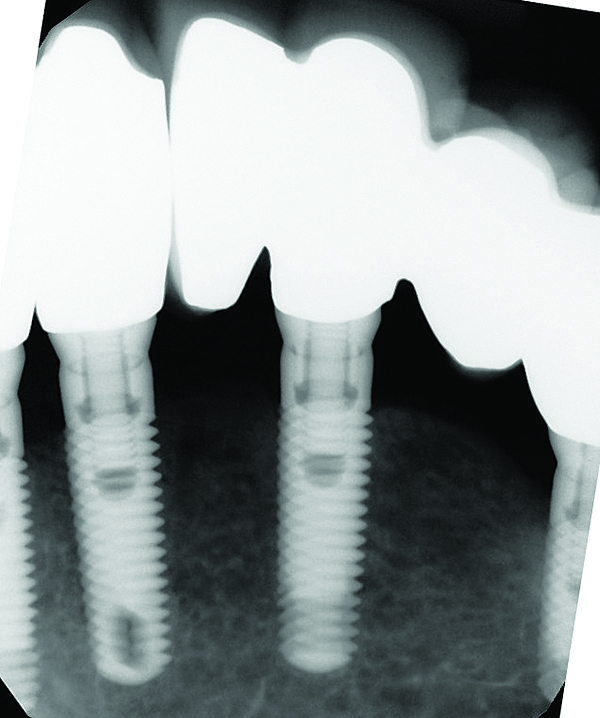

Fig 1 through Fig 6. Periapical radiographs of a 52-year-old man who received a fixed porcelain-fused-to-metal reconstruction supported by abutments attached to externally hexed dental implants. Fig 1 through Fig 3 are at initial prosthesis placement: maxillary right (Fig 1), textured surfaced threaded titanium implants at site Nos. 2, 4, and 6; maxillary anterior (Fig 2), implants at site Nos. 7 through 9; maxillary left (Fig 3), implants at site Nos. 12 and 14. Fig 4 through Fig 6 are 10 years post-insertion of the prosthesis: maxillary right (Fig 4), maxillary anterior (Fig 5), and maxillary left (Fig 6). Note minimal to no bone loss radiographically around the implants 10 years post-insertion of prosthesis.